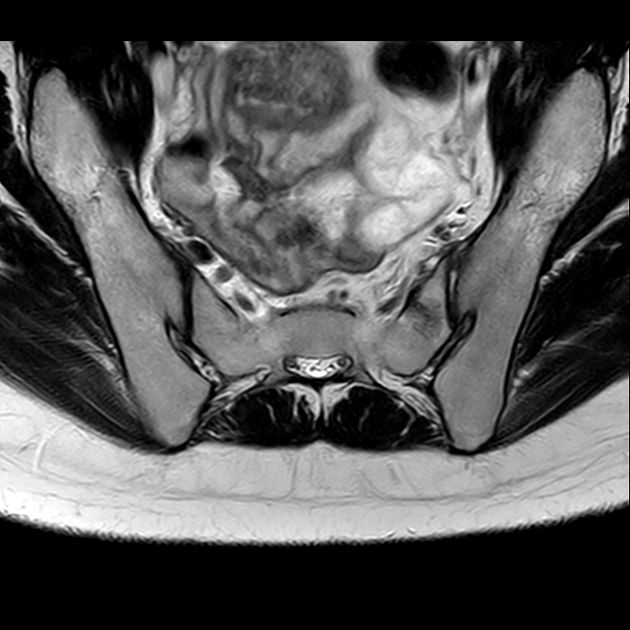

磁共振检查:

影像表现

2、单侧或双侧骶骨翼骨皮质断裂,见迂曲纵行骨折线,大致与骶髂关节平行(双侧多见);

3、骶骨体部看见骨折线

4、冠状位上述骨折形成 “H”型 ,故有人称东风本田征(为了方便记忆)

5、骨折线一般较为模糊,看见看到骨质硬化;

6、磁共振上可以发现骨折线周边明显的骨髓水肿,增强扫描明显强化

磁共振影像表现